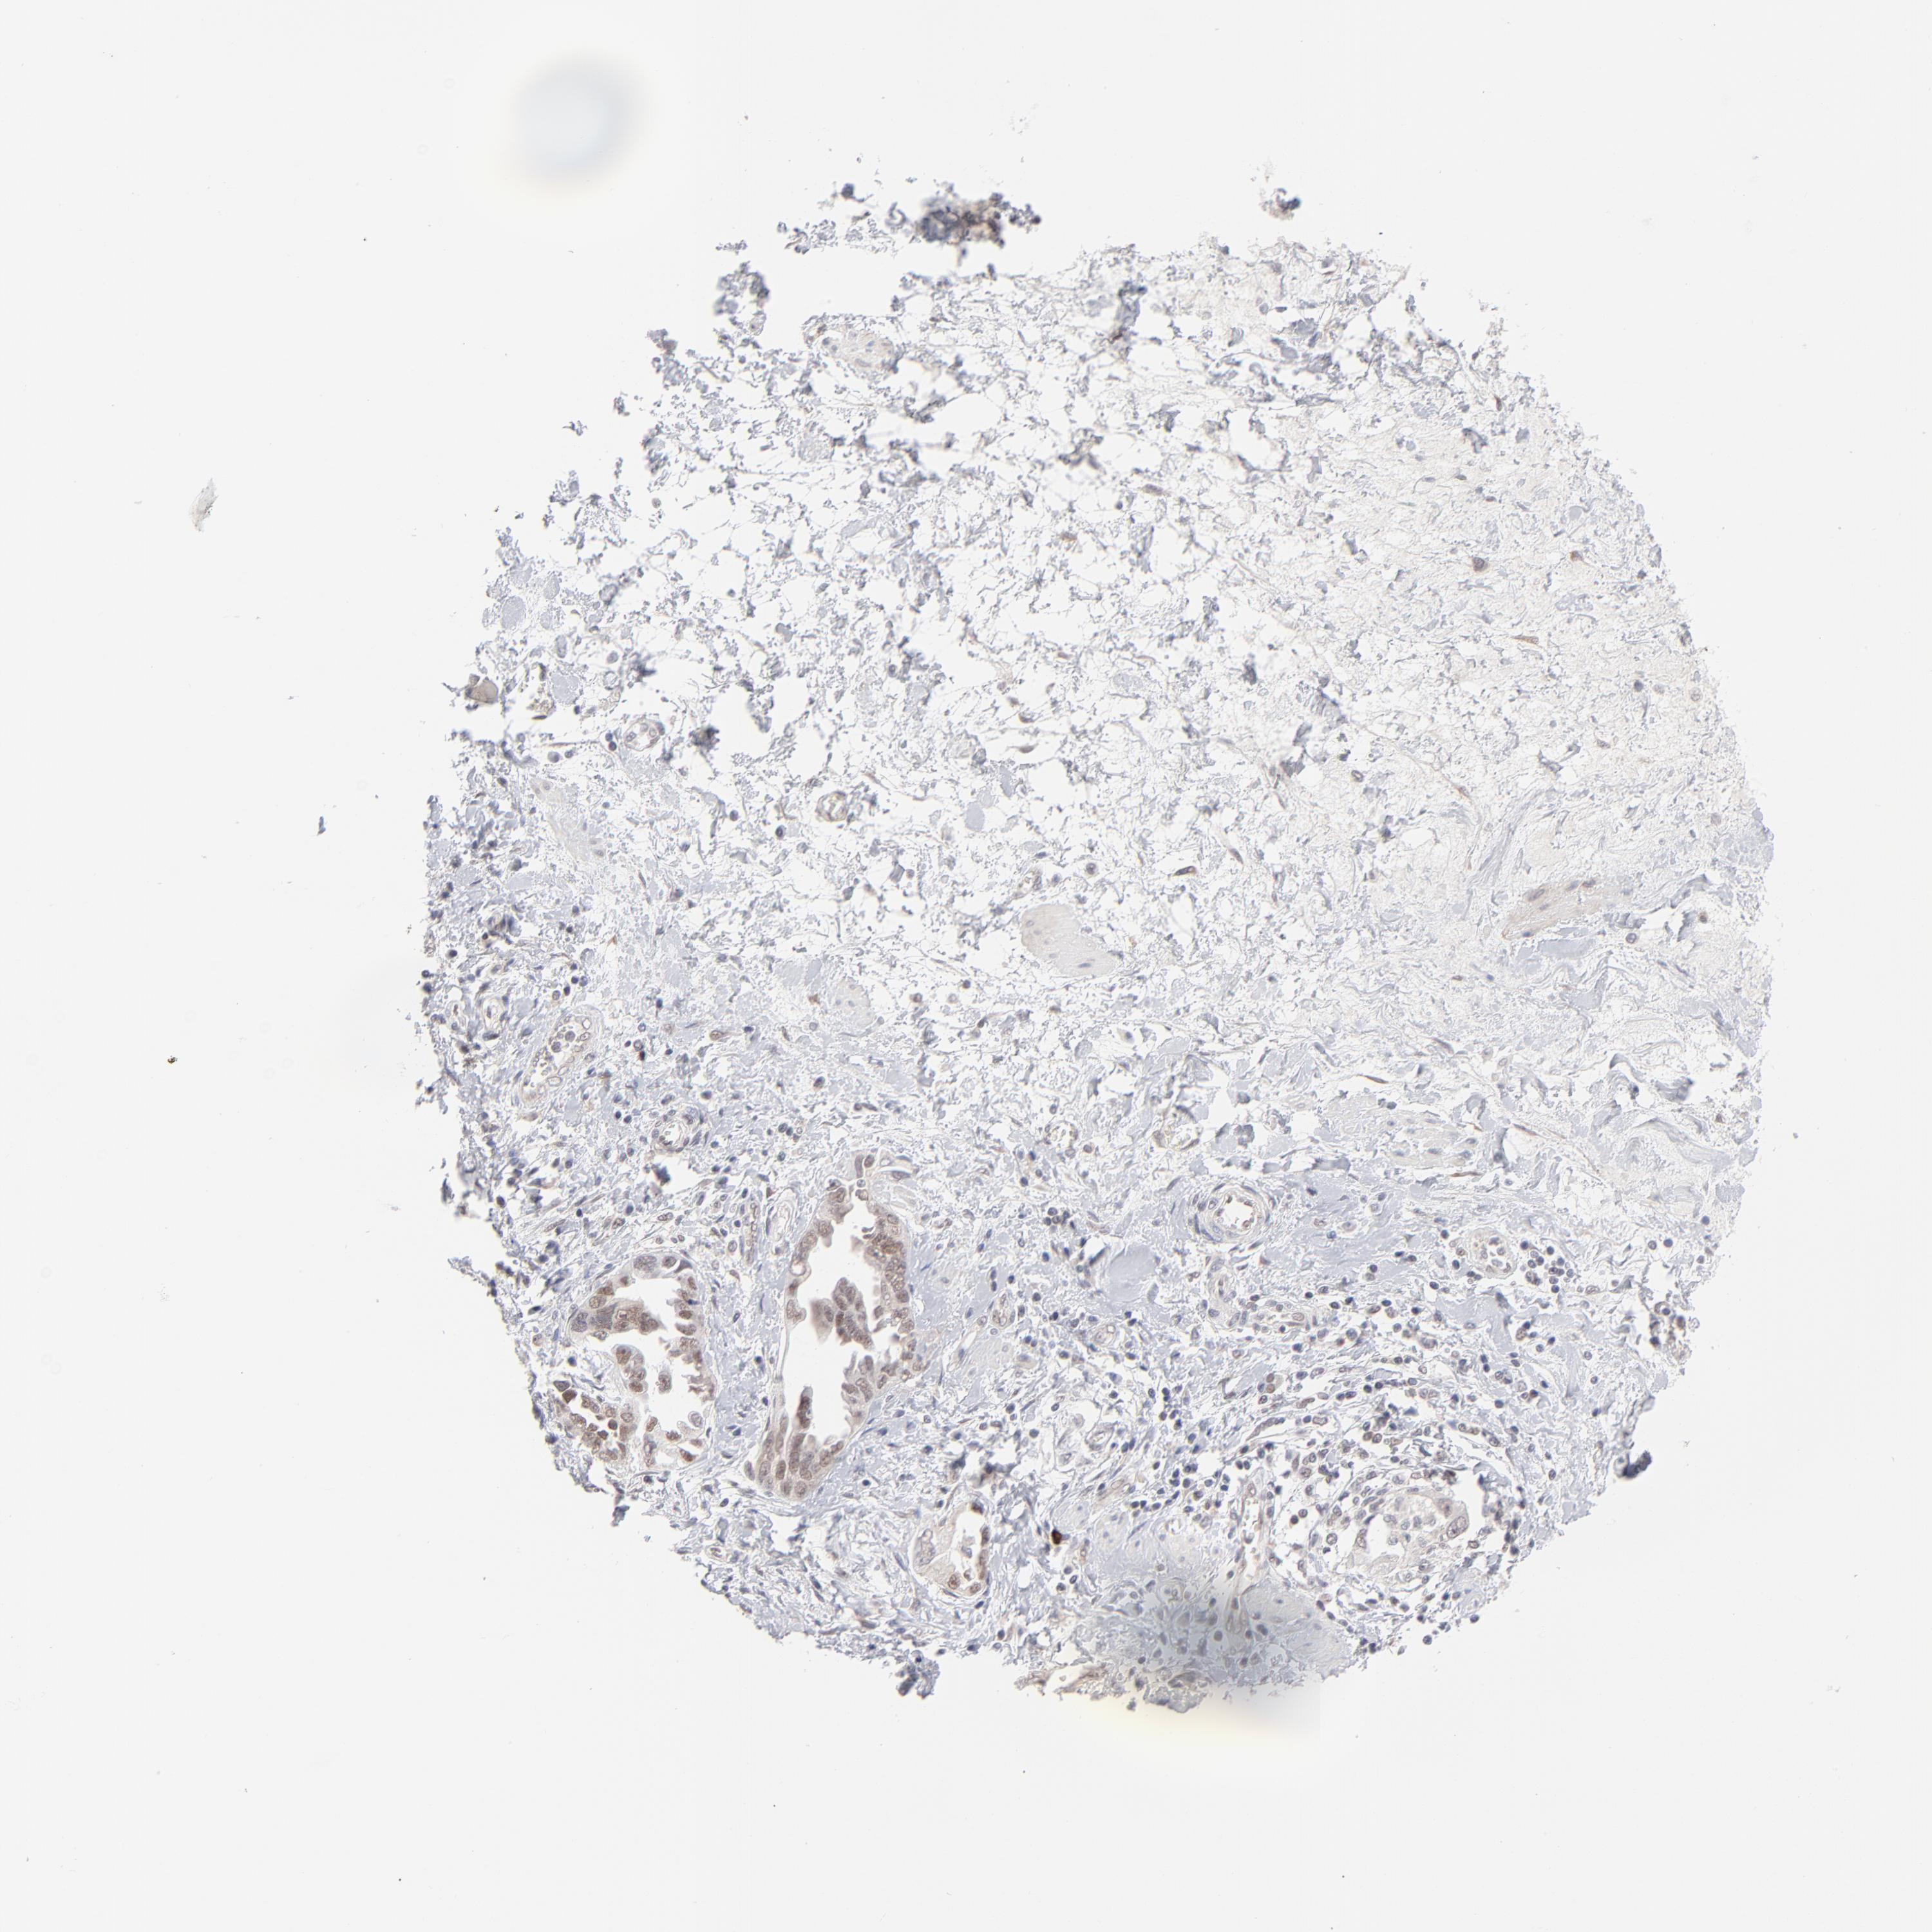

OVARIAN CANCER - Protein expressioni

A mouse-over function shows sample information and annotation data. Click on an image to view it in a full screen mode. Samples can be filtered based on level of antibody staining by selecting one or several of the following categories: high, medium, low and not detected. The assay and annotation is described here.

Note that samples used for immunohistochemistry by the Human Protein Atlas do not correspond to samples in the TCGA dataset.

Antibody stainingi

Antibody staining in the annotated cell types in the current human tissue is reported as not detected, low, medium, or high, based on conventional immunohistochemistry profiling in selected tissues. This score is based on the combination of the staining intensity and fraction of stained cells.

Each image is clickable and will lead to virtual microscopy that enables deeper exploration of all samples and also displays staining intensity scores, fraction scores and subcellular localization as well as patient and tissue information for each sample.

Antibody HPA001429

Staining

High

Medium

Low

Not detected

Intensity

Strong

Moderate

Weak

Negative

Quantity

>75%

75%-25%

<25%

None

Location

Nuclear

Cytoplasmic/membranous

Cytoplasmic/membranous,nuclear

Carcinoma, endometroid

Cystadenocarcinoma, serous, NOS

Cystadenocarcinoma, mucinous, NOS